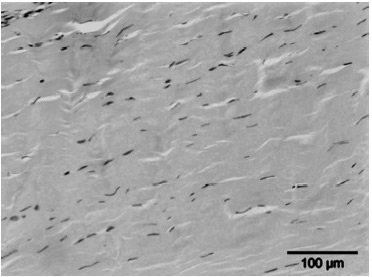

2) Weefselregeneratie

Een tweede hypothese is dat ESWT een positief effect heeft op weefselregeneratie door:

- De toename van neovascularisatie in de pees-bot overgang.

- Het opwekken van groeifactoren zoals vasculo-endothelial growth factor (vegf).

- Het stimuleren van de collageenproductie en het afvoeren van beschadigd collageen, wat resulteert in een verhoogde matrix-turnover.

- Het beïnvloeden van stamcelmigratie en -proliferatie via mechanotransductie.

- De stijging in de celpermeabiliteit. De stimulatie van de celdeling.